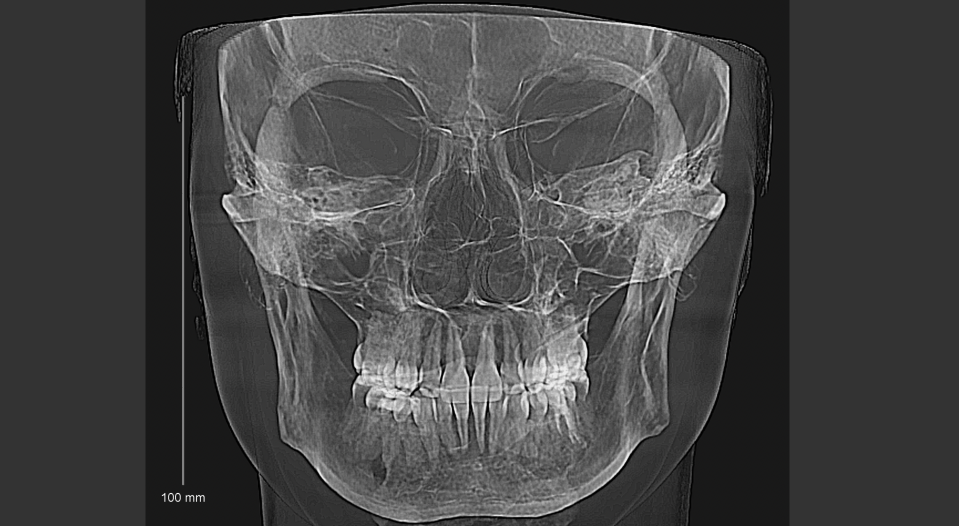

4. Развёрнутое 3Д-исследование ВНЧС и челюстей

Третий по счёту ортодонт сразу направила меня на развёрнутую 3D-цефалометрию — это КТ двух челюстей и височно-нижнечелюстного сустава. За это исследование я отдала ещё 7 700 рублей.

Забавно, что ортодонт, у которого я лечусь сейчас, считает его избыточным и вообще не нужным в моей ситуации. Ну да ладно. Сделано и сделано.